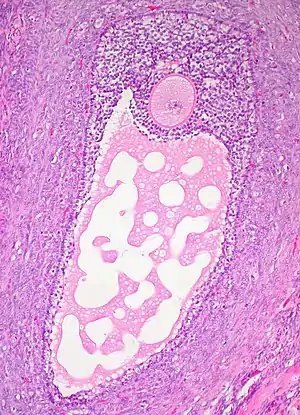

![]() Corte histológico de un folículo ovárico maduro. El ovocito es la célula grande, redonda, de tinción rosada en el centro superior de la imagen. | ||

Los folículos ováricos son las unidades básicas de la biología reproductiva femenina.[5] Consisten de una célula gamética, (el ovocito) rodeada de células diploides denominadas de la granulosa, y por fuera de estas se encuentran las células de la teca. Durante su desarrollo, esta unidad biológica llamada folículo, genera una estructura llamada antro, que se produce por la acumulación de líquido en su interior.[3]

Los folículos se encuentran en el interior del ovario.[2] Estas estructuras se activan periódicamente e inician su proceso de crecimiento y desarrollo para culminar, generalmente, en la ovulación de un solo ovocito viable. Estos ovocitos son envueltos por una capa de células llamada granulosa, encerradas en una matriz extracelular —la membrana folicular principal o lámina basal— que constituye el folículo ovárico.[3] Los folículos ováricos con mayor crecimiento, que son visibles a simple vista, son llamados folículos de De Graaf (en honor de su descubridor Regnier de Graaf).[6]

- Las células granulosas segregan mucopolisacáridos que forman un halo protector, la zona o membrana pelúcida alrededor del oocito. Este folículo, el folículo antral, crece hasta alcanzar un diámetro de unas 150 μm y presenta una cavidad entre las células granulósicas, que está llena de líquido folicular (rico en lípidos y algunas proteínas). Esta estructura, llamada antro, terminará rodeando completamente al ovocito hasta la ovulación.

- Una fase de folículos maduros: o folículos de Graaf que son de tipo antral, de gran tamaño en comparación a los otros tipos de folículos, y tienen varias capas de células de la granulosa..[9]

- Se forman de la siguiente manera: las prolongaciones citoplasmáticas de las células granulosas continúan penetrando en la zona pelúcida y proporcionan nutrientes y señales hormonales a los ovocitos primarios en maduración. Este paso es dependiente de FSH que, además de inducir la proliferación de las células de la granulosa, incrementa el número de receptores de éstas, potenciando su propio efecto. Además, parece ser que la LH dirige la diferenciación de las células tecales que rodean al folículo. El ovocito ahora se desplaza hacia una posición excéntrica y se rodea de una capa llamada cumulus oophorus o disco prolígero (de 2 o 3 células de grosor). Al final de esta fase el complejo folículo preovulatorio o de Graaf alcanza un diámetro medio de 2 a 5 mm. Son estos folículos los que llegan a la etapa de la ovulación.[8]